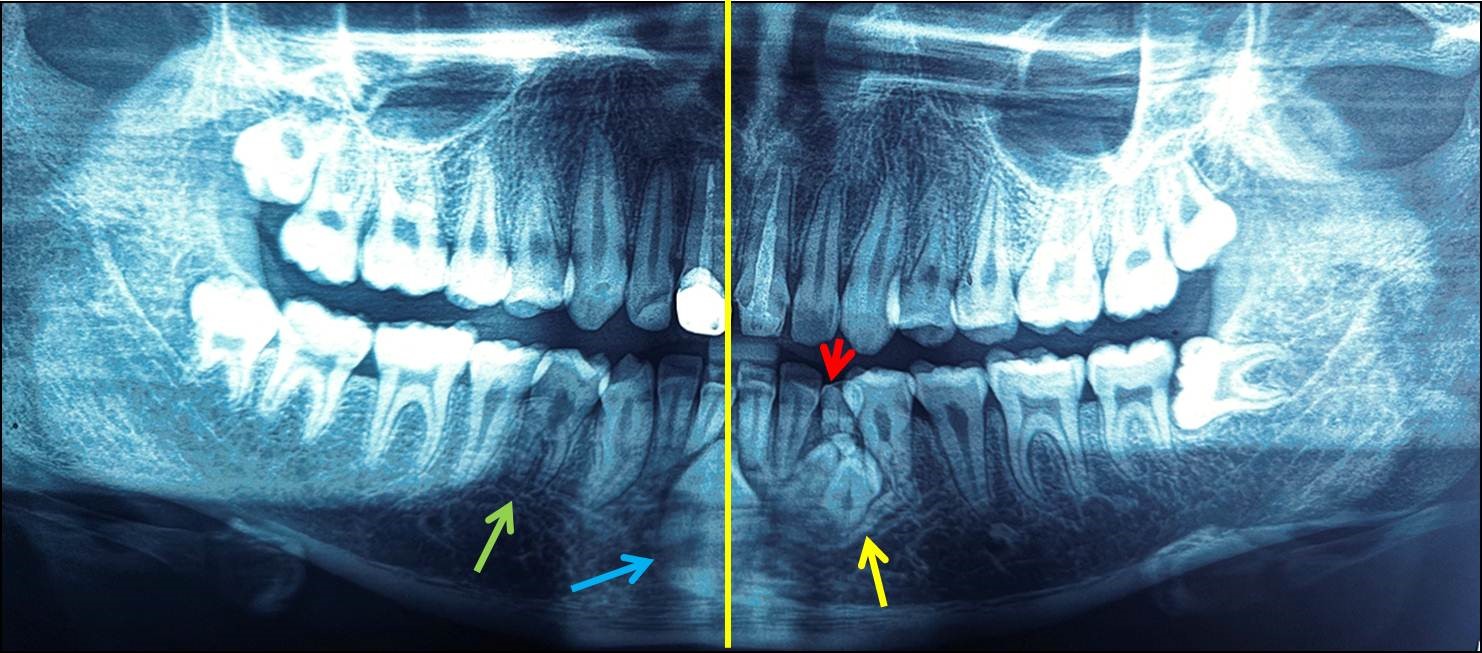

A 18-year-old male patient reported to the Department of Pediatric and Preventive Dentistry, College of Dental Sciences, Davangere, Karnataka, India complaining of dislodged restoration from upper front tooth. Patient was moderately built, well-nourished and did not exhibit any symptoms of systemic, syndromic or metabolic disorders. Patient past history revealed history of dental trauma at the age of 11 years followed by root canal treatment and crown placement for his upper both central incisors. From then patient did not visit dentist and now visited seeking treatment for his dislodged crown. Intraoral examination showed patient with complete permanent dentition except for the presence of retained 73. Permanent 33 was clinically missing. 73 exhibited some degree of mobility. To know the condition of 73 patient was subjected to radio-visuographic examination which revealed presence of small irregular shaped radiopaque masses below the root of 73 and in place of permanent left canine (Figure 1). Radiographic mass exhibited 3-4 small, tooth shaped structures resembling supernumerary teeth (Figure 1). Above these structures, a solitary, small, round shaped radiopaque structure was observed. Regarding root of 73, it exhibited apical one third of root resorption. In addition to these, radiograph also showed half picture of impacted tooth located between right and left central incisors. Hence, to have the complete image of the impacted canine, orthopantomography was taken. Examination of OPG showed rotated and vertically oriented impacted mandibular left canine, its long axis crossing the dental midline. The impacted canine was located below and between roots of two central incisors. Further evaluation of the radiograph showed presence of a supernumerary root in mandibular right first premolar. The two roots were mesial and distally located (Figure 2). Contralateral premolars had single roots. The root of the permanent mandibular right canine exhibited root flexion and aberrant morphology of the root canal Details of morphological oddities are explained in Table 2. No other dental findings were observed. To attend chief complaint of the patient, crown was re-cemented and patient was explained about the existing dental anomalies in his jaw. As all three dental anomalies were asymptomatic, not associated with any pathologic changes periodic observation was advised.

Figure 2:Panoramic radiograph showing bifurcated roots with 34 and 44 (green arrow), transmigrated 33 (blue arrow) crossing midline (yellow line) and impacted combined complex and compound odontome (yellow arrow). Retained 73 is also evident.

The credit of studying transmigrated canines and framing classification system goes to a great researcher Mupparapu [26]. He classified transmigrated canine into five types based on orientation of the transmigrated canine with dental midline and it is given only for mandibular canine (Table 3) [26]. Based on this classification, the transmigrated mandibular left canine in the present case was categorized as Type 5 as the impacted canine was positioned vertically at the midline below the roots of two central incisors with its long axis crossing the midline. There are drawbacks pointed out by other researchers in Mupparapu’s classification such as bilateral occurrence of canine transmigration is not taken into consideration [17,18]. Hence, a recent study formulated a new classification system (MBS) classification which classified transmigrated canines into main five types with further subdivisions based on several criteria like the distance travelled by the transmigrated canine, unilateral or bilateral occurrence and the axial angulation of the canine with the dental midline [27]. Precise classification of mandibular canine transmigration helps in planning appropriate treatment protocol. In this case, as the transmigrated canine was asymptomatic and located below and between the roots of two central incisors no treatment was performed and only periodic observation was suggested. In the present case, presence of odontoma perfectly indicates the exact etiology for the transmigration of permanent canine. Moreover, over-retained primary tooth also clearly indicates the possibility of impaction of the permanent canine and also indicates the presence of hidden dental pathology [19].